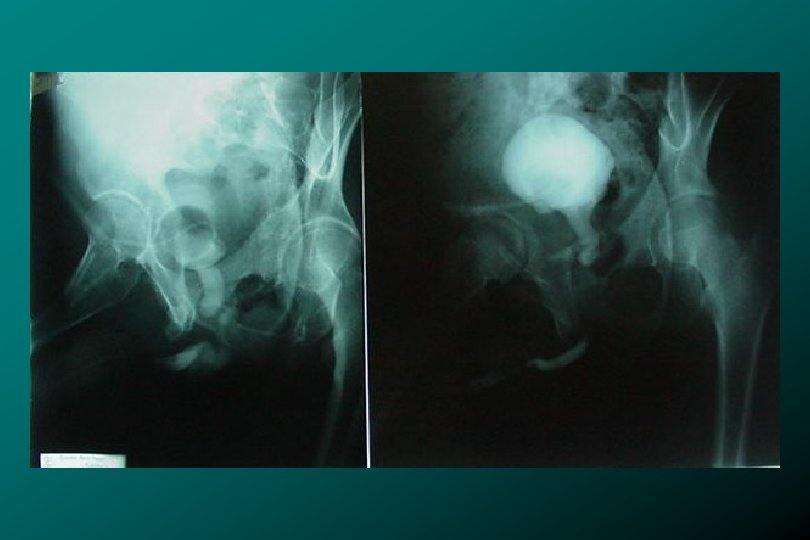

TRAUMA DE URETRA POSTERIOR CLASIFICACIÓN * Tipo I Estiramiento uretral (17%) * Zegarra L.

TRAUMA DE URETRA POSTERIOR CLASIFICACIÓN * Tipo I Estiramiento uretral (17%) * Zegarra L. : Traumatismos Urológicos. En: Barboza ed. Principios y Terapéutica Quirúrgica. Lima: De Arteta Imp. 1999: 576 -590.